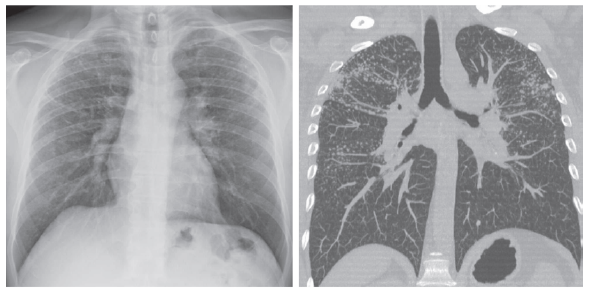

Complementarias: Es cierto que en algunos casos se puede requerir una tomografía computarizada (TC) de tórax de alta resolución para confirmar el diagnóstico de silicosis, especialmente cuando existen dudas o cuando la radiografía de tórax con técnica OIT no es concluyente. La TC de tórax de alta resolución proporciona imágenes más detalladas y precisas de los pulmones, lo que permite una mejor visualización de las lesiones pulmonares y una evaluación más precisa de la presencia y extensión de la silicosis13,50. En casos de sospecha de silicosis, si la radiografía de tórax con técnica OIT muestra una profusión de 1/0 o 1/1 pero se requiere una mayor certeza diagnóstica, el médico puede solicitar una TC de tórax de alta resolución12. Esta prueba puede revelar cambios característicos de la silicosis, como nódulos, fibrosis y engrosamiento pleural, que pueden ser más evidentes en comparación con la radiografía de tórax convencional. Es importante mencionar que la interpretación de la TC de tórax debe ser realizada por un radiólogo experimentado en enfermedades pulmonares y, en algunos casos, puede ser necesaria una evaluación adicional por parte de un neumólogo especializado. Ver imagen 2.

Imagen 2 Diferencia entre radiografía de tórax con técnica OIT y Tomografía computadorizada de tórax de alta resolución (TCAR). Imágenes gentiliza de reproducción del Dr. Anselmo López Guillén y Dr. Sergio Rovira Sans.